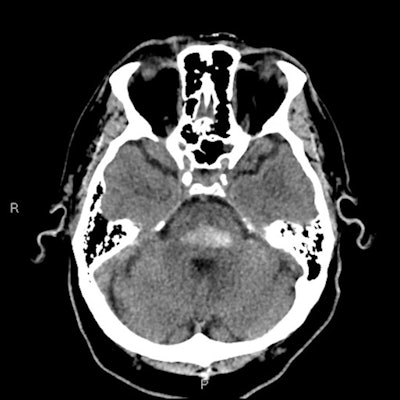

Hypoxic brain injury is an unfortunate consequence of drug addiction and especially drug overdose. Any illegal drugs are central nervous system (CNS) depressants, and overdose can lead to respiratory depression, respiratory arrest, and subsequent hypoxia. The early findings in CT are those of cerebral edema. Some drugs such as heroin have a vasospastic effect that can produce focal infarcts, and for those who survive the event, the long-term appearances are varying degrees of cerebral atrophy, the researchers explained.

"Cocaine causes cerebral vasospasm, and significantly reduces cerebral blood flow," they pointed out. "Cocaine abuse is also associated with both parenchymal and subarachnoid hemorrhage, which are twice as common as ischemic events."